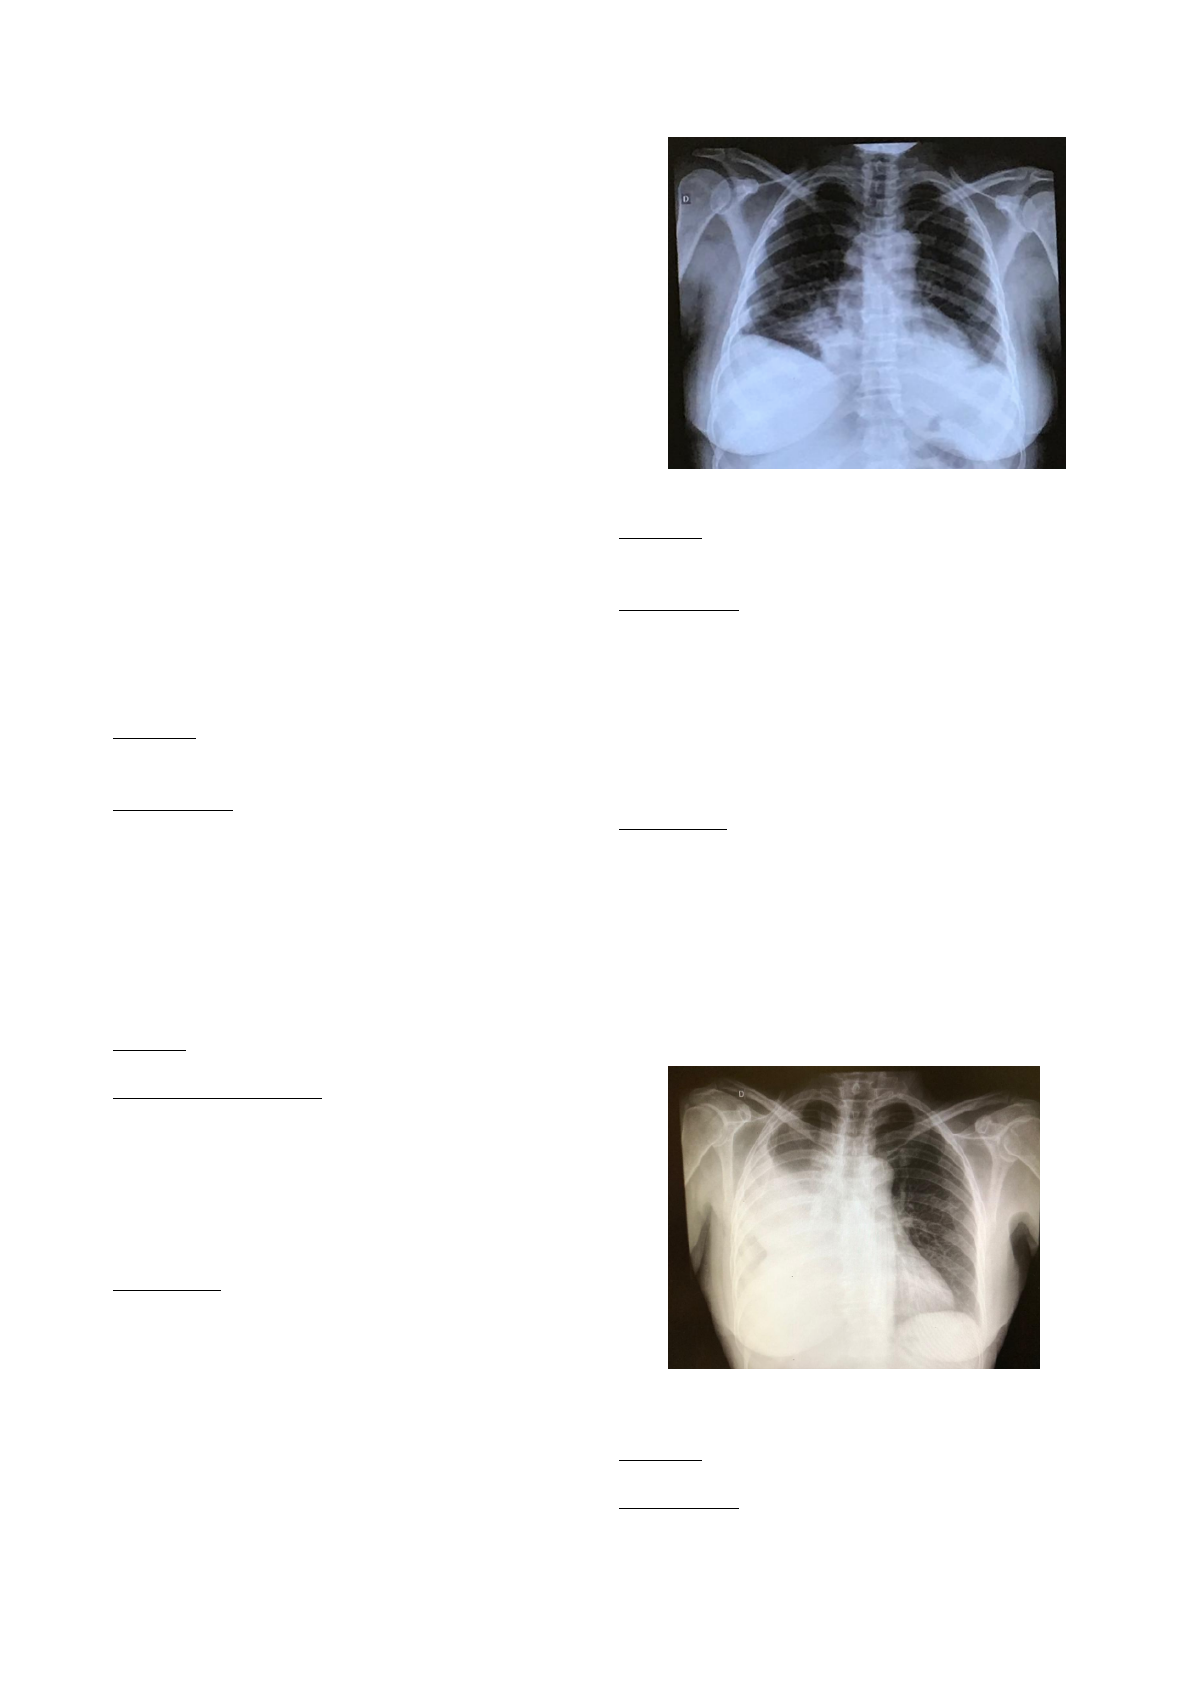

2.Derrame pleural

Etiologia:

-acumulo de líquido entre as superfícies pleurais

Radiografia:

Se tem a presença de líquido na região afetada,

este fica em forma de U